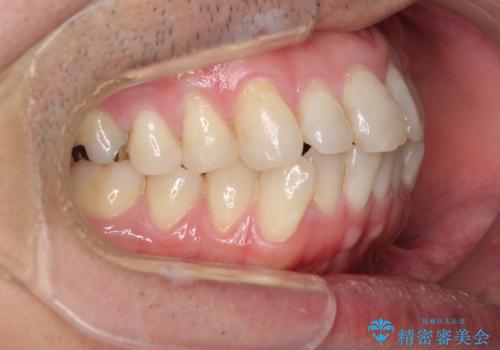

ボロボロとなっていた歯は抜歯が必要な状態でしたが、舌側転位している歯を移動させることで抜歯スペースを埋めることができるため、矯正治療により歯列を整えることとしました。

舌側転位の改善にインビザラインを用いるのはやや難易度が高くなりますが、前歯部のデコボコは軽度であったため、インビザラインによる矯正治療を行うこととしました。

矯正治療後には抜歯が必要な歯に隣接してむし歯となっていた歯をオールセラミッククラウンにて補綴治療を行うこととしました。

矯正治療開始時に、インビザライン矯正の加速装置を購入されましたが、インビザライン自体をあまりしっかりと使用できず、4年間の治療期間となりました。